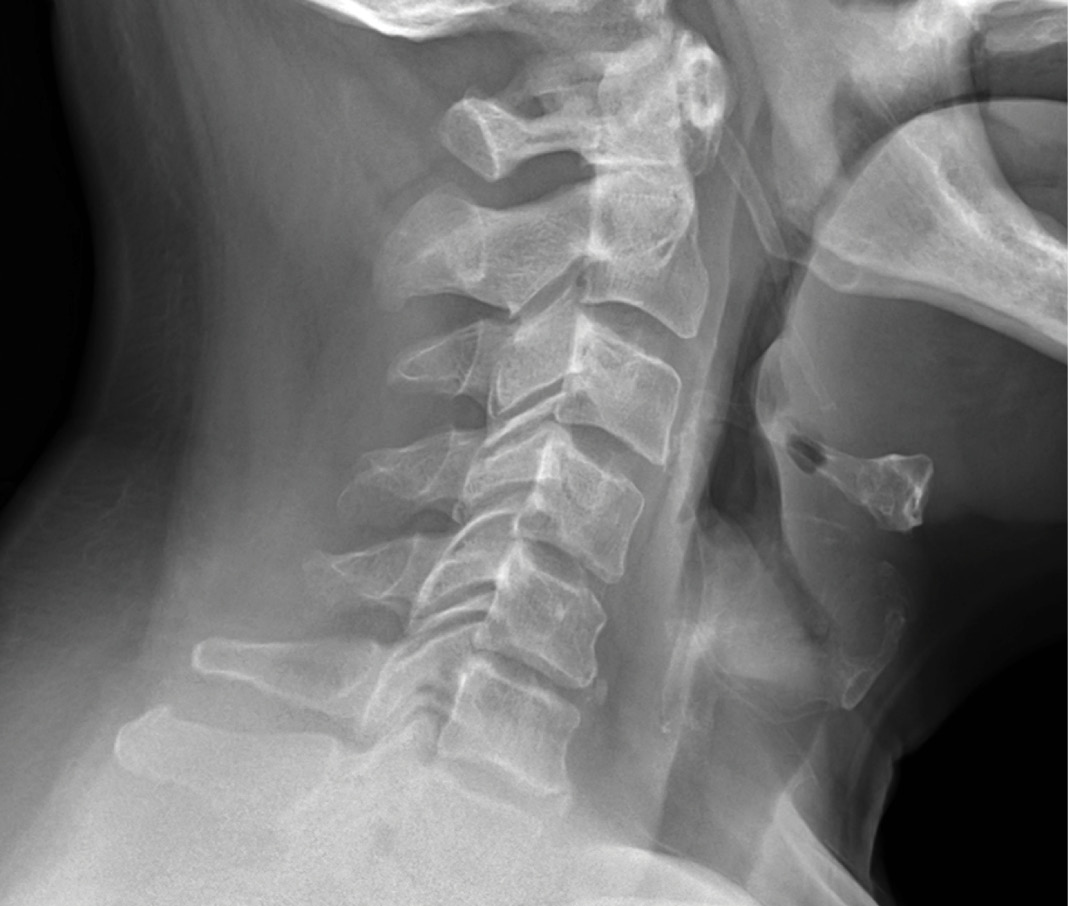

The patient presented with right shoulder and arm radiculopathy.

He had weakness on exam in the right deltoid and biceps. The patient had no left arm symptoms at all.

MRIs illustrated mild degenerative disc disease from C4-6 with disc herniations at both C4-5 and C5-6. The axial slice through C4-5 showed a right central disc herniation causing central and mainly right-sided foraminal stenosis. The axial slice through C5-6 showed a central disc herniation also causing central and mainly right-sided foraminal stenosis. The axial slice through C6-7 showed a left-sided disc herniation causing some left-sided foraminal stenosis, however, the patient did not demonstrate any left-sided symptoms.

Upon examination, the patient had good motion on flexion-extension, so fusion was not considered at all. My operative plan was to use prodisc cervical devices and replace both discs at C4-5 and C5-6, giving me the flexibility to use either a domed or flat implant.